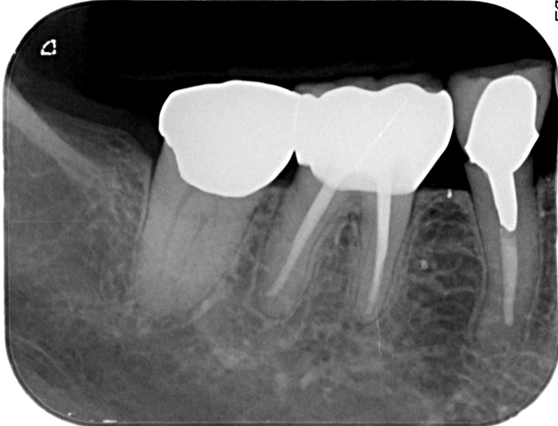

意図的再植術

意図的再植術は、歯根の先端に感染源がある場合、一度、歯を抜いてから感染源を切り取りし、再び歯を戻す治療法です。歯根端切除術と同様の治療目的ですが、歯根端切除術が適応外の部位に行います。